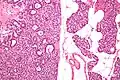

![]() Микропрепарат: слева — аденома паращитовидной железы, справа — неизменённая ткань паращитовидной железы (окраска гематоксилин-эозином). | |

Микропрепарат паращитовидной железы: аденома слева (окраска гематоксилин-эозином). -

Паратиреоаденомы из главных клеток образованы крупными полигональными клетками. Цитоплазма их слегка базофильная, мелкозернистая. Ядра крупные полиморфные, встречаются и гигантские, уродливой формы. Строма нежная, обильно васкуляризирована. Критерий наличия аденомы — атрофированная паратиреоидная ткань под капсулой или за ней, а также невозможность обнаружения остальных паращитовидных желез или наличие атрофированных желез. Ультраструктура опухолевых клеток свидетельствует об их высокой функциональной активности и об утрате нормального секрето́рного цикла. В цитоплазме секреторные гранулы и гипертрофированный комплекс Гольджи. Хотя практически во всех клетках выявляется гликоген — нормальные реципрокные взаимоотношения с секреторными гранулами утрачены. В клетках паратиреоаденом в отличие от обычных паратиреоцитов не выявляется цитоплазматический жир[1].

В верхних паращитовидных железах чаще встречаются водянисто-клеточные аденомы, образованные крупными «пустыми» клетками с мелкими гиперхромными яюрами. В них встречаются ацинарные и фолликулярные структуры. Электронная микроскопия выявляет в цитоплазме вакуоли — производные комплекса Гольджи с признаками усиленного синтеза и секреции паратгормона. В физиологических условиях «водянистые» клетки встречаются только у новорожденных[1].